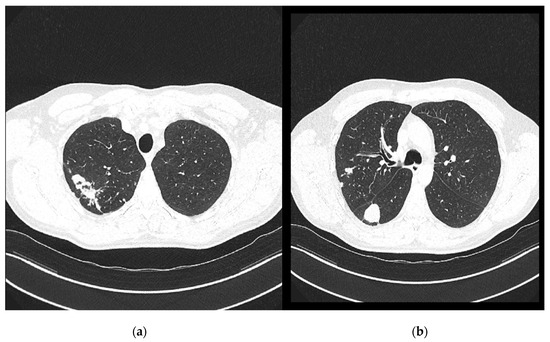

On 7 November 2024, a follow-up contrast-enhanced MSCT of the thorax was performed and compared with the previous CT scan from 29 April 2024 (Figure 4). It revealed several irregular, confluent solid lesions in the right apical region, the largest measuring 23 mm, 29 mm, and 20 mm in diameter, consistent with tuberculomas. Band-like fibrotic changes extending to subpleural and perifocal areas were also noted. In addition, micronodular interstitial changes and a “tree-in-bud” pattern were present, along with several solid parenchymal nodules up to 5 mm in diameter, suggestive of miliary tuberculomas. A tuberculoma measuring 26 × 26 mm was identified in the upper segment of the right lower lobe, with subpleural localization. Only a few reactive lymph nodes remained, with the largest measuring 9 mm in diameter.

Figure 4. Chest CT scans (7 November 2024): (a) solid lesions in upper lobe; (b) tuberculoma in the upper segment of the right lower lobe.